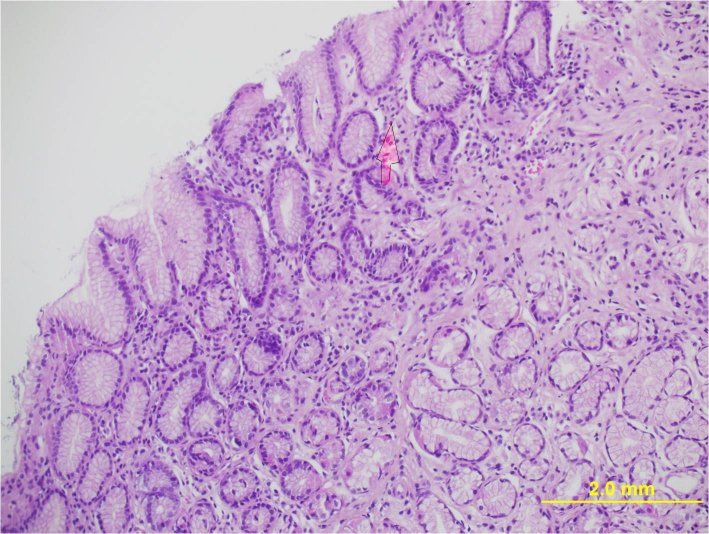

A 30 year old male presented to our clinic with history of on and off epigastric pain of 4 years duration without any alarming symptoms. The patient had no history of offending drug intake. He had been taking proton pump inhibitors Tab. Esomeprazole 20 mg twice daily continuously for 4 years with partial relief. He has been a non smoker and denied any drug abuse or alcohol intake. His systemic examination was unremarkable. He was evaluated on outpatient basis. He had haemoglobin of 14 g/dl with normal leucocytic count and normal platelet count. He had normal liver and kidney function tests. Serum amylase was within normal limits. Abdominal ultrasound showed a normal size of the liver with its normal echo texture. There were no gall stones, the common bile duct was normal and other abdominal viscera were also normal. The patient underwent upper gastrointestinal (GI) endoscopy which revealed a normal esophagus and a small hiatal hernia. There were multiple polyps in the antral area, each around 1 cm (Figure 1 [Fig. 1]). A biopsy was taken from these polyps and a Campylobacter-like organism (CLO) test was also done. The patient's biopsy (Figure 2 [Fig. 2]) revealed evidence of chronic gastritis with no H. pylori activity. The polyp was adenomatous with no features of malignancy. His serology for H. pylori was negative. The patient had a normal colonscopic examination and familial polyposis was ruled out.

Figure 2: Histology of the polyp